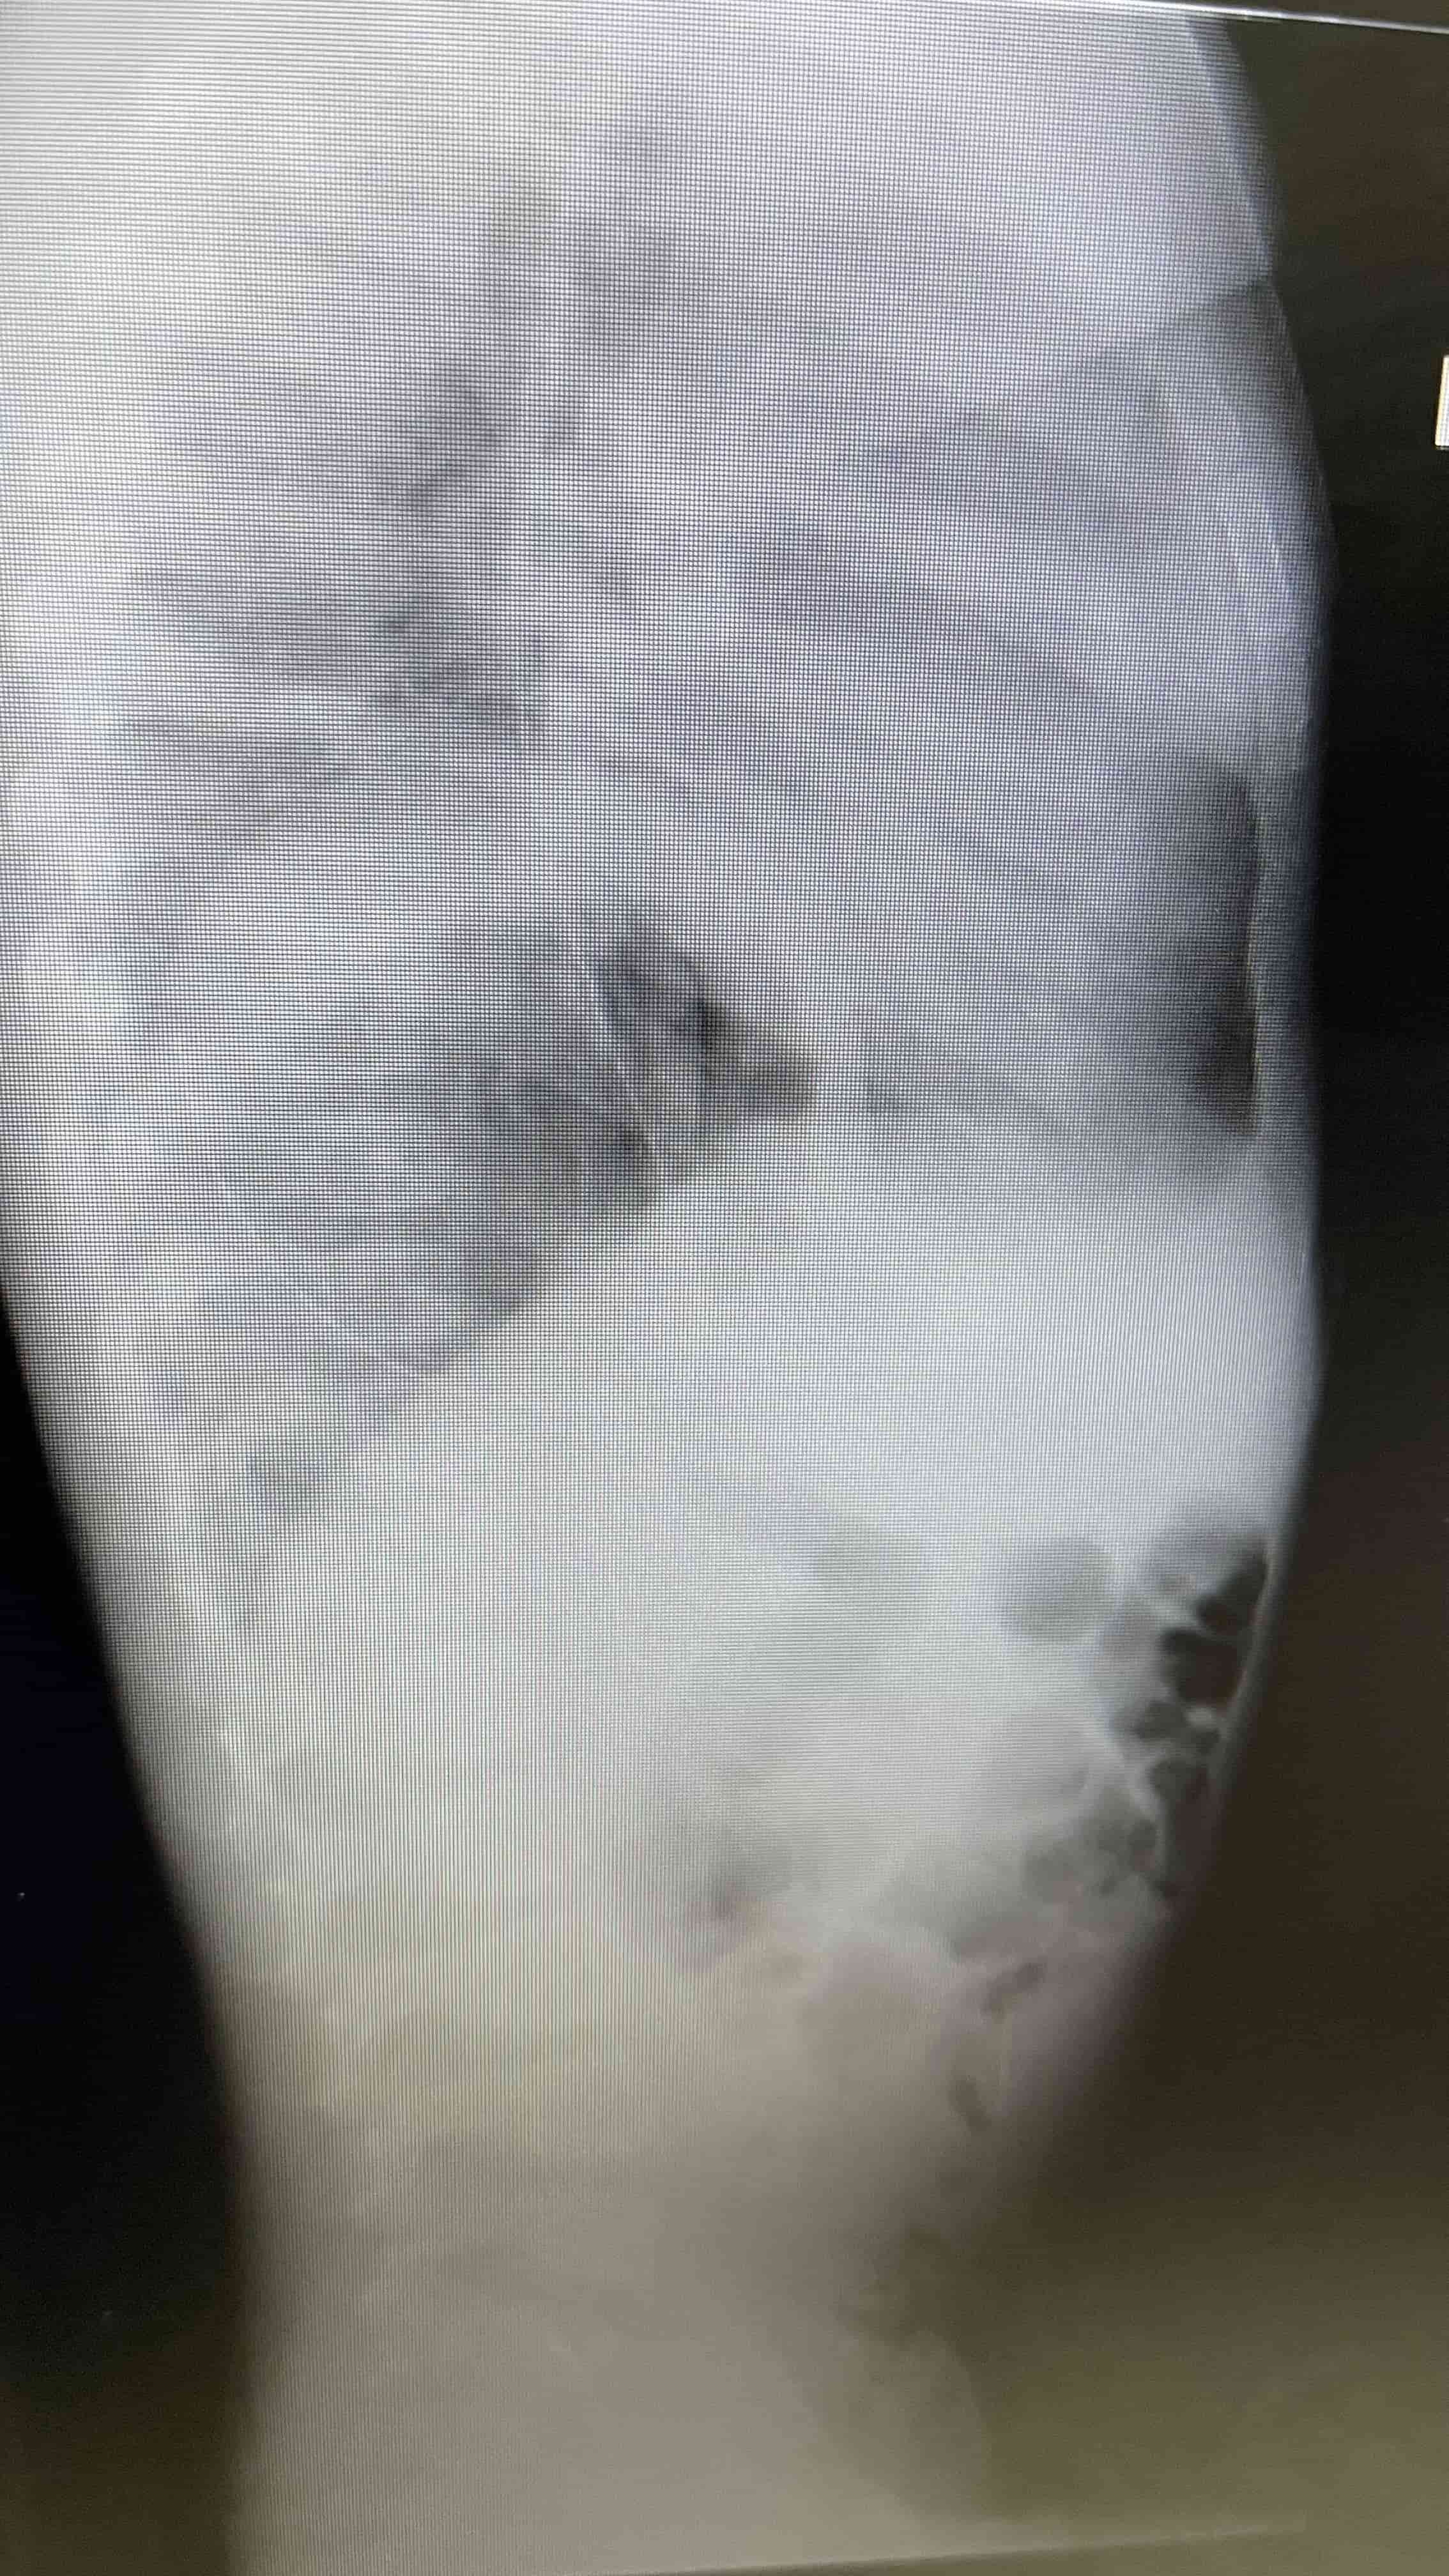

Médicos salvan la vida de infante con hernia diafragmática y estómago desplazado hacia los pulmones Radiografía de pecho y abdomen, luego de tratamiento con tubonasogástrico. Se demuestra mejoría marcada en desplazamiento deestructuras mediastinales. Médicos salvan la vida de infante con hernia diafragmática y estómago desplazado hacia los pulmones Placa lateral portable, se demuestra la hernia diafragmática Médicos salvan la vida de infante con hernia diafragmática y estómago desplazado hacia los pulmones Placa de pecho portable luego de reparación quirúrgica del diafragma.

"Tuvimos que analizar rápidamente diagnósticos diferenciales para rápido llegar al punto de lo que le estaba causando todos estos síntomas a la paciente. Se le realizaron placas de pecho y de abdomen, y ahí nos percatamos, junto a la ayuda del radiólogo, que esta paciente tenía una hernia diafragmática y que gran parte de su estómago estaba distendido y desplazado hacia el lado izquierdo del pecho, donde se supone que va el pulmón. Ahí entendimos las dificultades que atravesaba entre las náuseas, sueño y la dificultad respiratoria posicional", detallaron.

Continuaron explicando que, debido a que el estómago de esta paciente estaba distendido y lleno de aire, el diafragma presentaba un defecto al fungir como el músculo que separa los pulmones del abdomen.

"El estómago estaba tan inflamado y lleno de líquido, que empujaba las estructuras mediastinales y esto provocaba una disminución en la cantidad de sangre que llegaba al cuerpo. Tuvimos la bendición de que contamos con la ayuda del radiólogo, quien nos informó que tenía un Gastrotórax a tensión, que empujaba al mediastino hacia el lado contrario donde estaba el estómago, ocupando el espacio del lado izquierdo del pulmón, y esto demandó rápido un tubo nasogástrico -utilizado para la obstrucción intestinal-inmediatamente", establecieron.